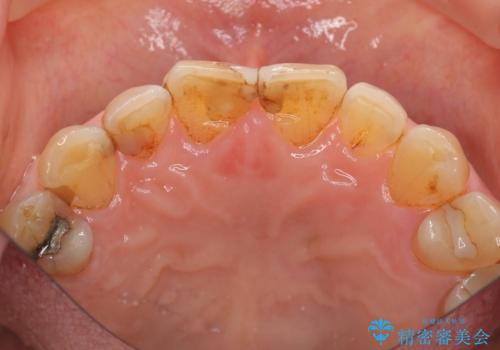

目立つ前歯の変色を改善したい

- 前歯の小さな虫歯を複数回治療した結果、つぎはぎだらけになってしまい審美的な改善を求めて来院されました。

これ以上のコンポジットレジン修復は更なる審美障害を招きかねないので、全体を覆うセラミッククラウンを選択します。

ディープバイト・噛み合わせが強いことからフルジルコニアクラウンを選択しました。